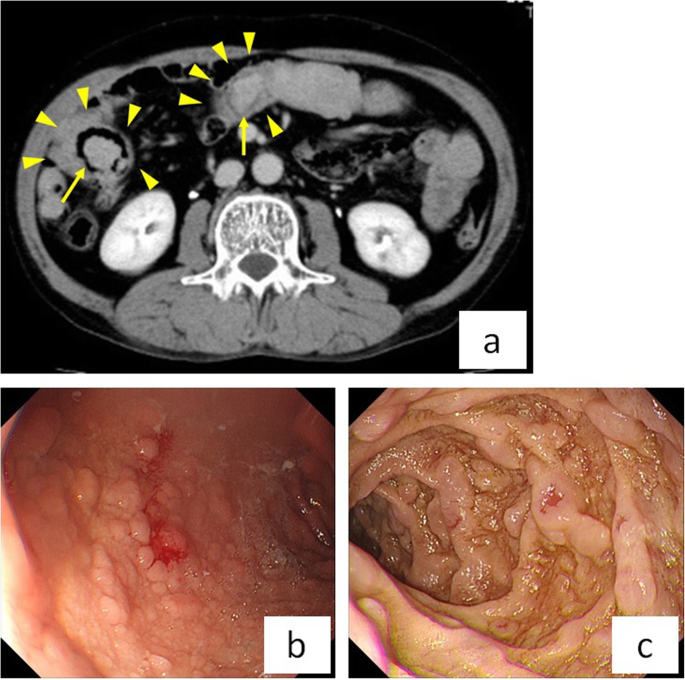

A 62-year-old male had a history of hypertension, hyperlipidemia, hyperuricemia, benign prostatic hyperplasia, and hepatic dysfunction. He was hospitalized for treatment of deep vein thrombosis (DVT) and pulmonary embolism (PE) with heparin and factor Xa inhibitor. Magnetic resonance imaging showed that DVT extended from both the left external iliac vein and the right femoral vein to the periphery (Supplementary Fig. 1a). PE involved an artery in the right lower lung, and echocardiography showed no pulmonary hypertension (Supplementary Fig. 1b). DVT and PE were caused by protein C deficiency type 2. Since the patient had progressive anemia (hemoglobin 11.1 to 8.0 g/dl for 11 days) and fecal occult blood testing was positive, gastrointestinal hemorrhage was suspected. The results of the hematological examination are shown in Supplementary Table 1. Although he had mild constipation about every 3 days, he was able to eat and had no abdominal pain. In the small intestine, computed tomography (CT) showed multiple intussusceptions and polyps (Fig. 1a). Upper gastrointestinal fiberscopy demonstrated multiple polyposis of the stomach and duodenum (Fig. 1b). The polyps were not actively bleeding, but bled easily with contact. On physical examination, the patient had numerous areas of pigmentation on his lips, fingers, and toes (Fig. 2a-c). Based on the above findings, he was diagnosed with PJS. Since the small intestinal polyps were thought to have caused gastrointestinal bleeding and multiple small intestinal intussusceptions that increase the risk of future bowel obstruction, we decided to perform laparoscopic disinvagination of the small intestine.